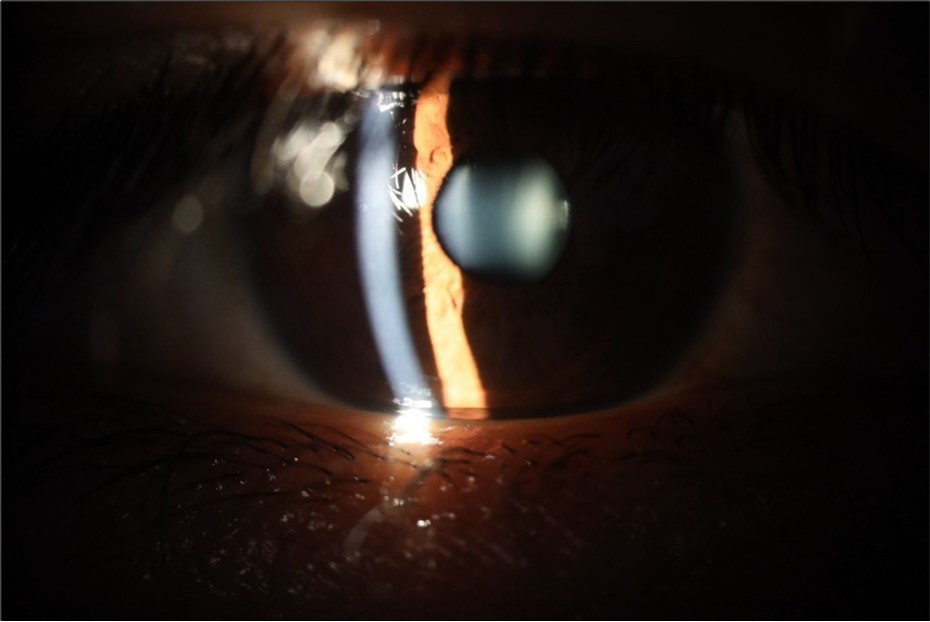

Figure 5.The slit-lamp photograph shows the anterior segment, relatively unscathed, in terms of transparent media (Cornea, crystalline and vitreous).

Figure 16.The anterior segment of the right eye shows the vitreous with greater transparency. The cornea and lens, as well as the anterior chamber, are in good condition.